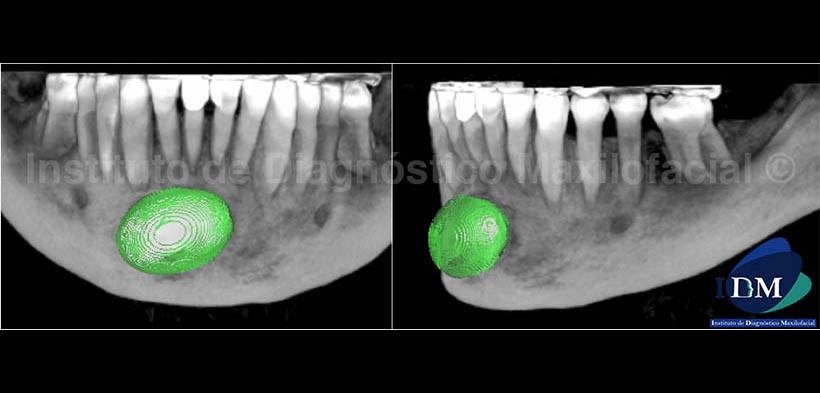

En las vistas tridimensionales (Fig. 5) se observa el lecho quirúrgico de bordes lisos y perfectamente delimitado (A), así mismo en la proyección de máxima intensidad se aprecia la neoformación ósea recubriendo el implante aloplástico (B); y por ultimo, con el filtro radiográfico (Fig. 6) ilustramos el implante de color verde para el mejor entendimiento de su posición y ubicación con respecto a la zona anterior del maxilar inferior.